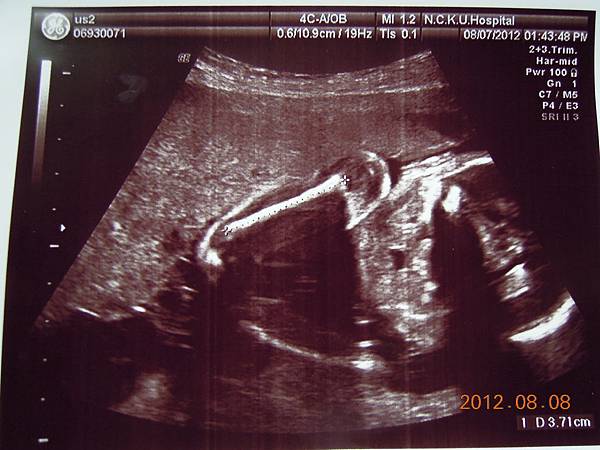

這個好像是逼逼的臉吧~~

這張可以看到他的厚嘴巴~~我回來拿給Horry看,說他跟你的嘴巴一樣ㄟ~~他聽了一直笑~~~

接下來就是他的一堆檢查照片啦~~